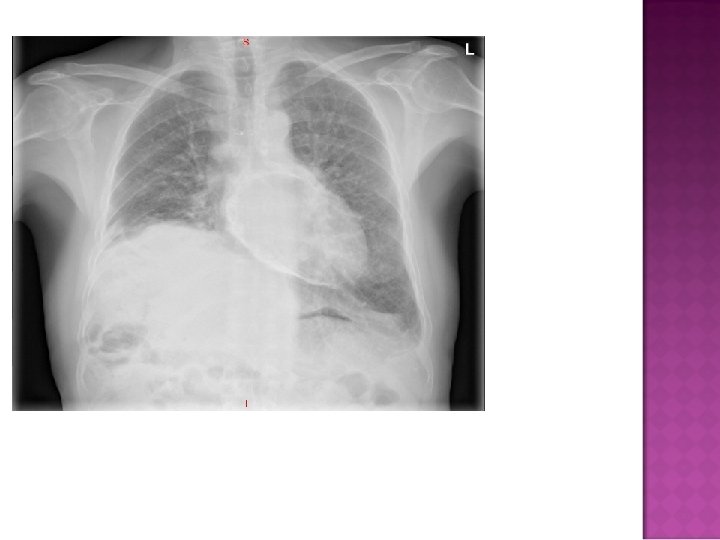

Cardiomegaly due to a massive pericardial effusion. At least 200 m. L of pericardial fluid must accumulate before the cardiac silhouette enlarges.

Sudden inc in size of cardiac silhouette w/o specific chamber enlargement Effacement of the normal cardiac borders Development of a “flask” or “H 2 O-bottle” shaped heart

Normal in patients with acute pericarditis unless pericardial effusion is present Enlarged cardiac silhouette Requires 200 cc of fluid